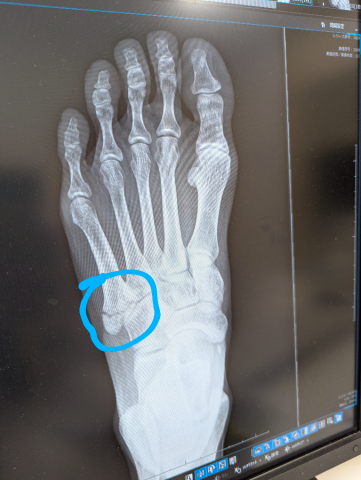

夜道で転倒して

左足の甲を骨折してしまいました?

第5中足骨骨折または下駄骨折というらしいです